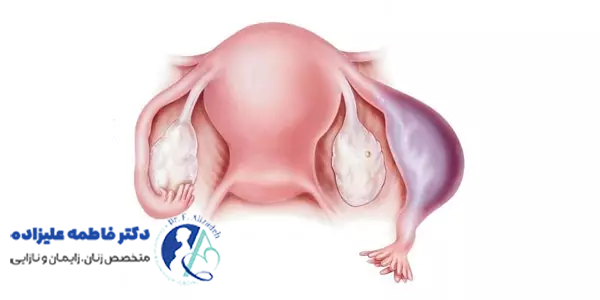

درمان چسبندگی رحم با هدف بازگرداندن شکل طبیعی حفره رحمی، بهبود قاعدگی و افزایش شانس باروری انجام میشود. روش اصلی و استاندارد درمان، هیستروسکوپی جراحی است. در این روش، پزشک با استفاده از هیستروسکوپ و ابزارهای ظریف، چسبندگیها را مستقیما مشاهده و با دقت برش میدهد.

بعد از عمل، برای جلوگیری از ایجاد چسبندگی مجدد، از روشهایی مثل قرار دادن یک کاتتر یا بالون داخل رحم یا تجویز استروژن برای ترمیم بهتر مخاط استفاده میشود. در برخی موارد، انجام چندین جلسه هیستروسکوپی و پیگیری مداوم لازم است. همچنین، فیزیوتراپی لگن و درمانهای دارویی کمکی، در بهبود وضعیت و پیشگیری از عود موثر میباشد. انتخاب روش درمان بسته به شدت چسبندگی، شرایط بیمار و برنامه بارداری او تعیین میشود.

پیشگیری از چسبندگی رحم بعد از جراحی، یکی از نکات مهم برای حفظ سلامت رحم و باروری در زنان است. بعد از جراحیهایی مثل کورتاژ، سزارین، برداشتن فیبروم یا سایر اعمال داخل رحمی، مراقبت مناسب و رعایت برخی اقدامات، احتمال ایجاد چسبندگی را کاهش میدهد. استفاده از تکنیکهای جراحی دقیق و ظریف توسط پزشک برای کاهش آسیب به بافت رحم از اولین گامهای پیشگیری است.

همچنین، گاهی پزشک از روشهایی مثل گذاشتن بالون، اسپیرال یا ژلهای مخصوص در داخل رحم برای جلوگیری از چسبیدن دیوارهها به یکدیگر استفاده میکند. تجویز داروهای ضد التهاب یا هورمونی در برخی موارد هم به ترمیم بهتر مخاط رحم کمک میکند. پیگیری دقیق وضعیت رحم با سونوگرافی یا هیستروسکوپی در دوره بعد از جراحی، به شناسایی زود هنگام چسبندگیها و درمان آنها قبل از بروز عوارض کمک میکند.